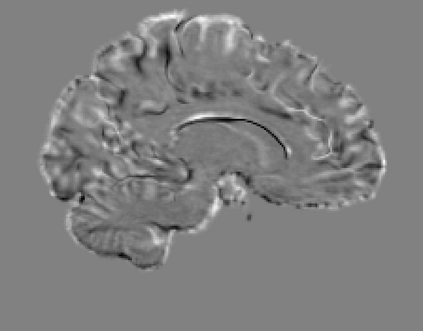

The purpose of this work is to contribute to the state of the art of deep-learning methods for diffeomorphic registration. We propose an adversarial learning LDDMM method for pairs of 3D mono-modal images based on Generative Adversarial Networks. The method is inspired by the recent literature for deformable image registration with adversarial learning. We combine the best performing generative, discriminative, and adversarial ingredients from the state of the art within the LDDMM paradigm. We have successfully implemented two models with the stationary and the EPDiff-constrained non-stationary parameterizations of diffeomorphisms. Our unsupervised and data-hungry approach has shown a competitive performance with respect to a benchmark supervised and rich-data approach. In addition, our method has shown similar results to model-based methods with a computational time under one second.